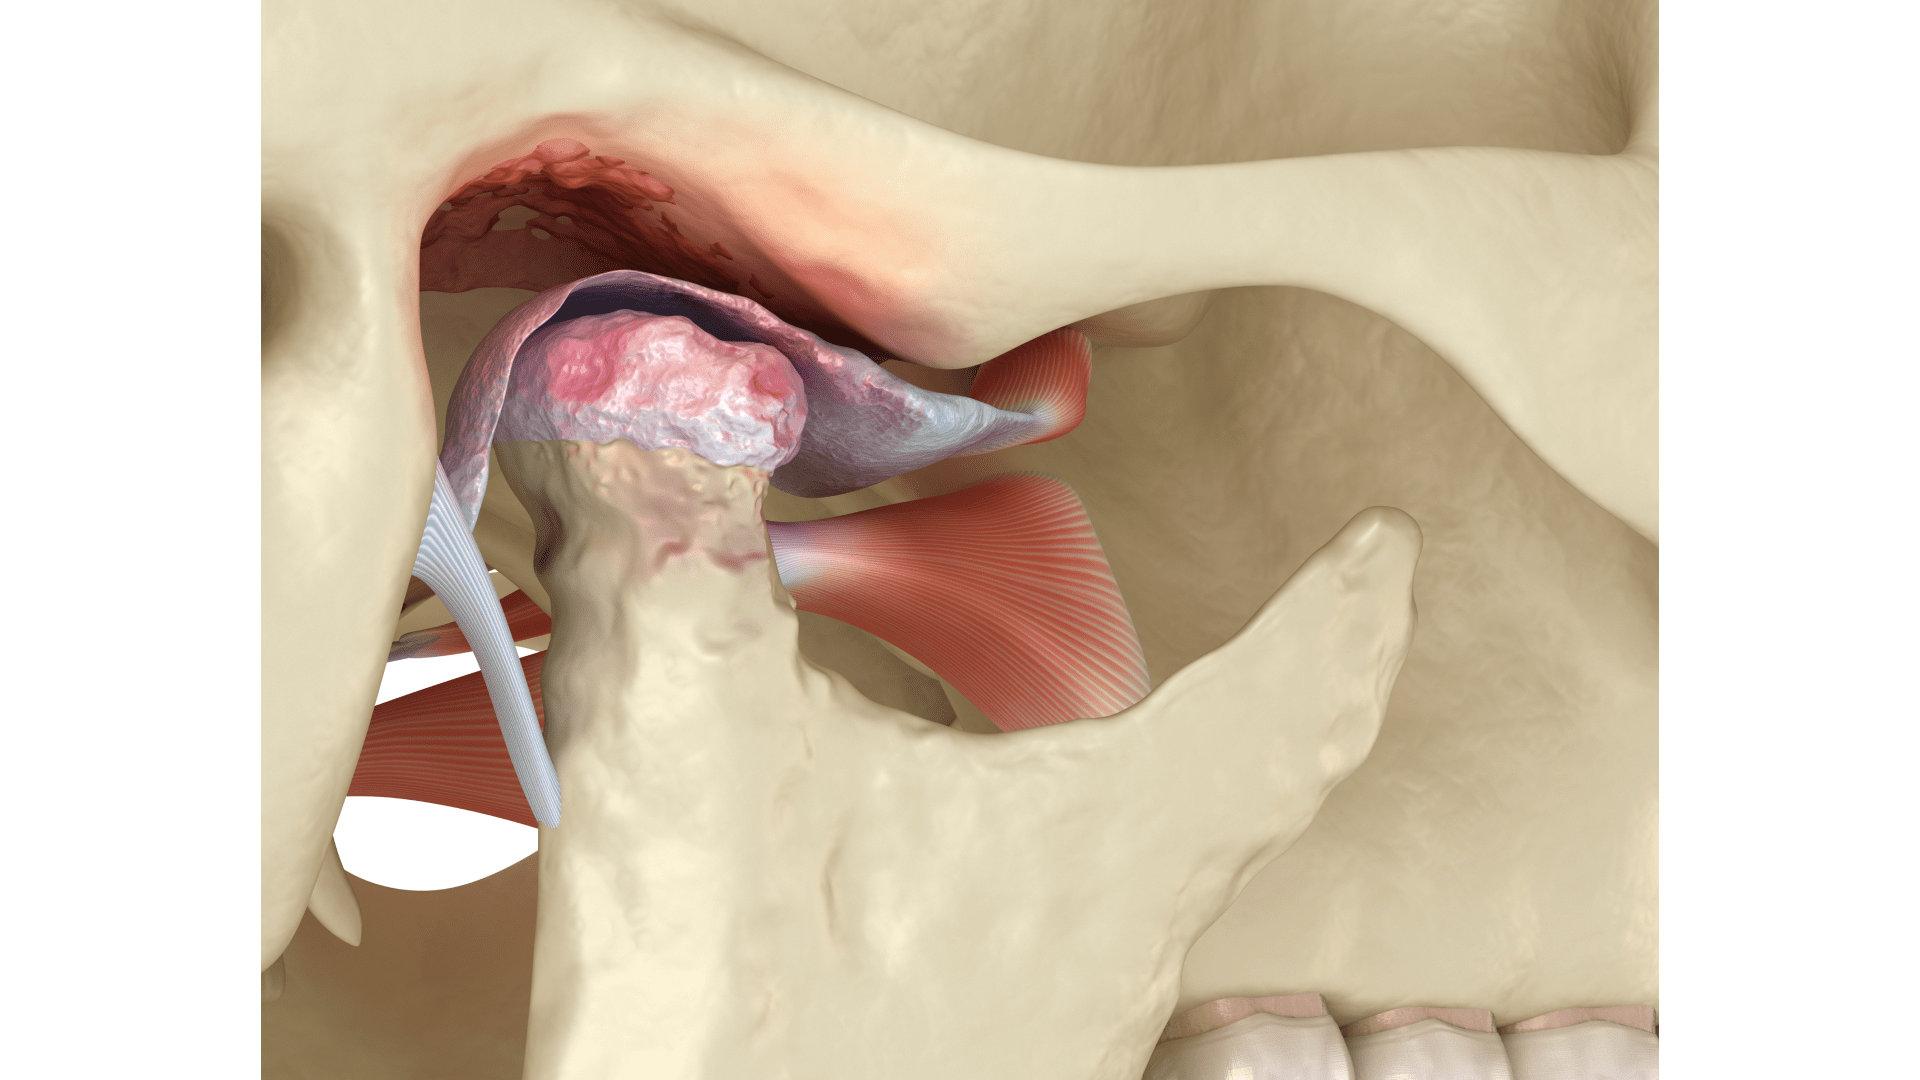

Методи лікування дисфункції СНЩС

Залежно від отриманих результатів досліджень лікування дисфункції скронево-нижньощелепного суглоба може бути:

- Консервативним. Застосовуються спеціальні знеболювальні та протизапальні ліки, а також ортодонтичні конструкції (суглобова шина, капа) для зниження навантаження на суглоб та відновлення його функції.

- Реконструктивним. Коригується прикус та проводяться ортодонтичні процедури для відновлення нормальної функції суглоба і запобігання його подальшому пошкодженню.

- Хірургічним. Проводяться артроскопічні операції або виконується ендопротезування суглоба для відновлення рухливості СНЩС у разі серйозних ушкоджень чи дегенеративних змін.